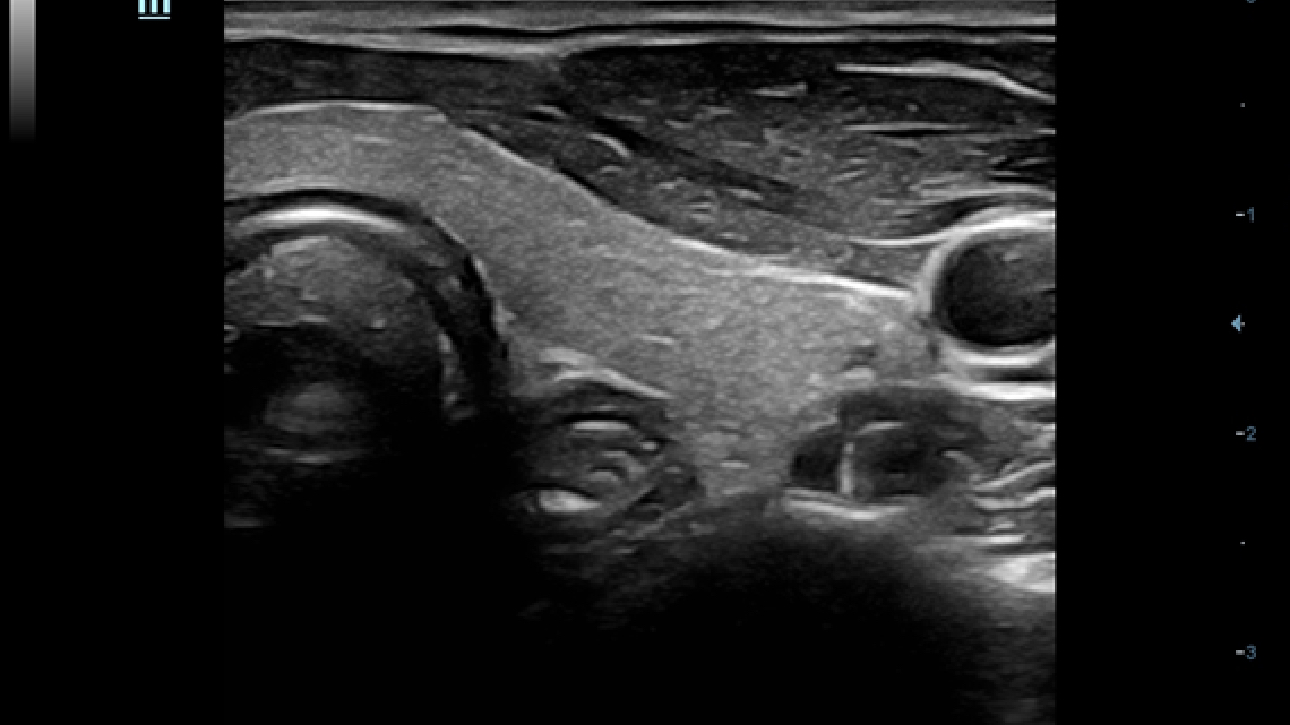

ComboWave-Schallköpfe

Im Vergleich zu herkömmlichen

Linear-Schallköpfen verwenden wir ComboWave- Schallsonden mit einem neuen Typ von piezoelektrischem Verbundwerkstoff. Damit gelingt es, das akustische Spektrum gezielt zu opti-mieren und die Impedanz zu reduzieren. Auf den ComboWave-Linear-Schallköpfen ist die einzigartige 3T-Technologie von Mindray integriert. Sie ermöglicht eine eXtreme Leistungsbreite bei sehr präziser Bildauflösung. Daraus resultierend wird eine Gleich förmigkeit des B-Bildes generiert, die unter anderem in Schild-drüsen-, Brust- und Gefäßanwendungen bestens unterstützt.

dc-60-exp-fig1

Optimierte Sonden mit 3T-Technologie